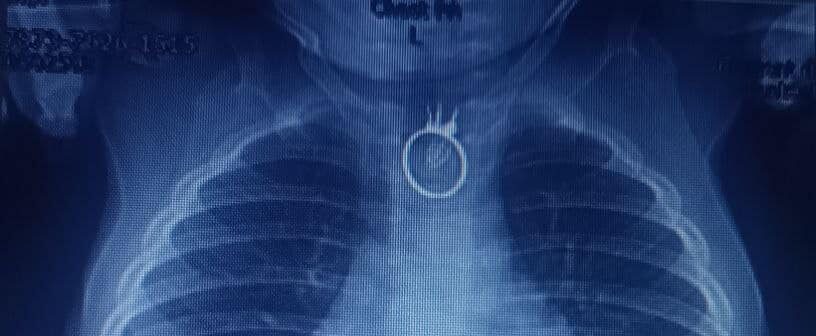

У Львові хірурги успішно провели операцію 10-місячному хлопчику, який проковтнув іграшковий перстень. Про це повідомили у лікарні “Охматдит”.

Тож вони одразу вирушили до місцевої лікарні у Новому Роздолі. Там лікарі зробили малюкові рентген, на якому побачили сторонній предмет. Дитину негайно каретою швидкої допомоги доставили до “Охматдиту”.

“Одразу після госпіталізації, о другій ночі, ми взяли дитину на операційний стіл і провели ригідну езофагоскопію з видаленням стороннього тіла. Це був перстень. Все пройшло успішно та без особливостей. Єдине, що іграшковий перстень трохи пошкодив стравохід”, – розповів дитячий хірург Олександр Колодій.